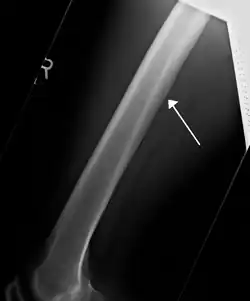

A nutrient canal feeding the femur seen on X-ray

All bones possess larger or smaller foramina (openings) for the entrance of blood-vessels; these are known as the nutrient foramina, and are particularly large in the shafts of the larger long bones, where they lead into a nutrient canal, which extends into the medullary cavity. The nutrient canal (foramen) is directed away from the growing end of bone. The growing ends of bones in upper limb are upper end of humerus and lower ends of radius and ulna. In lower limb, the lower end of femur and upper end of tibia are the growing ends.[1] The nutrient arteries along with nutrient veins pass through this canal. A nutrient canal is found in long bones, in the mandible, and in dental alveoli.[2] In long bones the nutrient canal is found in the shaft.